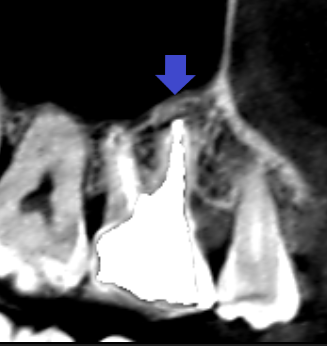

実際に「根管」の画像をご覧頂きましょう。歯の中にある黒い筋が根管です。